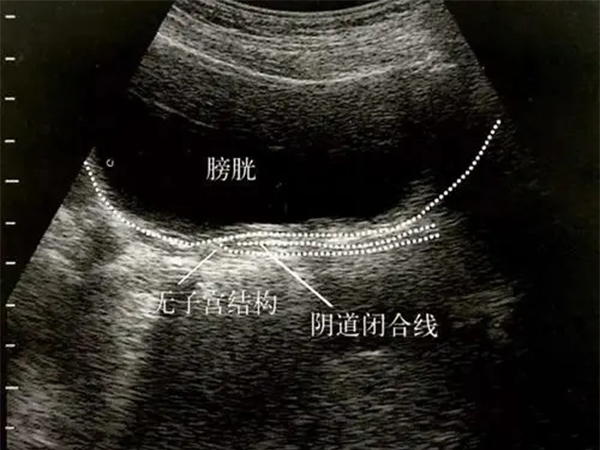

始基子宫超声诊断标准详解,看到无宫腔影像时得当心

始基子宫是一种先天发育的子宫畸形,与正常子宫相比始基子宫大多是合并无阴道,无子宫的,从而始基子宫的患者也不会有月经来潮,因此如果女性在18岁以前还不来月经就建议去..

幼稚子宫和始基子宫不一样!超声表现可看出区别在哪里

幼稚子宫和始基子宫是不一样的两种子宫畸形问题,医生通常是从超声结果来判定是始基子宫还是幼稚子宫。幼稚子宫的超声表现是子宫各径线明显比正常要小,前后径小于2cm,宫..